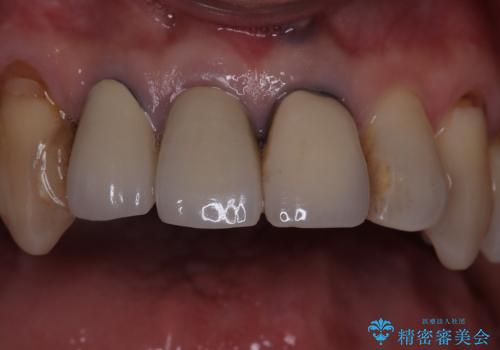

前歯を綺麗にしたい

- 昔入れた前歯を綺麗にしたいことを主訴に来院された患者様です。

根尖に病変を認めたため、根管治療を行いセラミッククラウンにて修復を行なっています。

根管充填はMTAにて行なっています。